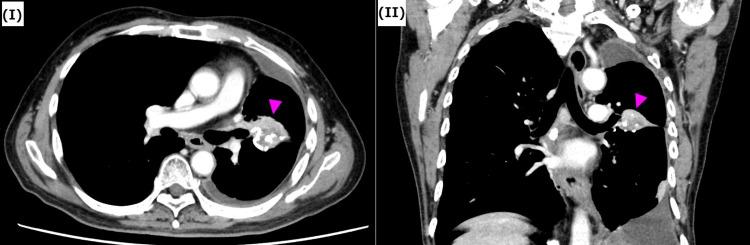

Thoracic re-irradiation has a high risk of severe adverse events, and re-irradiation with curative intent has rarely been performed. However, in recent years, with the introduction of intensity-modulated radiation therapy (IMRT) and stereotactic body radiation therapy, it has become possible to deliver high doses to the target lesions while minimizing the doses to surrounding tissues. The patient in this case had a history of definitive radiation therapy for esophageal cancer. The patient developed new lung cancer, which was treated by re-irradiation. We created a radiation treatment plan using IMRT. This allowed us to reduce the dose to organs at risk and deliver a higher dose to the cancer, increasing the potential for cure. The patient has not experienced any severe late adverse events as of three years and six months after treatment. Additionally, the treatment has been sufficiently effective, and the patient remains recurrence-free. To confirm the feasibility of the IMRT plan, we also created a radiation treatment plan using three-dimensional conformal radiation therapy (3D-CRT) and compared it with the IMRT plan. Compared with 3D-CRT, the IMRT plan was able to reduce the dose to organs at risk and meet the dose constraints indicated in multiple studies. The possibility of adverse events such as bronchial hemorrhage, esophageal hemorrhage, bronchial fistula, radiation pneumonitis, esophageal fistula, and pericarditis was significantly reduced.

胸部再程放疗有发生严重不良事件的高风险,且很少进行有治愈意图的再程放疗。然而,近年来,随着调强放射治疗(IMRT)和立体定向体部放疗的引入,在将周围组织剂量降至最低的同时向靶病变给予高剂量已成为可能。该病例患者有食管癌根治性放疗史。患者新发肺癌,接受了再程放疗。我们使用IMRT制定了放射治疗计划。这使我们能够降低危及器官的剂量,并向癌症给予更高剂量,增加治愈的可能性。截至治疗后三年零六个月,患者未出现任何严重的晚期不良事件。此外,治疗效果充分,患者仍无复发。为确认IMRT计划的可行性,我们还使用三维适形放疗(3D-CRT)制定了放射治疗计划,并将其与IMRT计划进行比较。与3D-CRT相比,IMRT计划能够降低危及器官的剂量,并满足多项研究中指出的剂量限制。支气管出血、食管出血、支气管瘘、放射性肺炎、食管瘘和心包炎等不良事件的可能性显著降低。